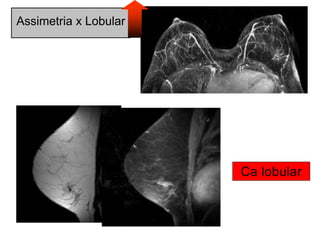

• Assimetrias x lobular

Assimetria x Lobular